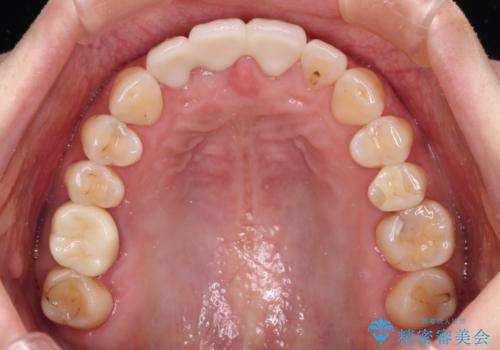

折れているのに応急処置でごまかしてきた前歯 オールセラミックブリッジによる補綴治療

- 歯根が破折しているにもかかわらず、抜歯を避けてきたため痛みが発現したとのことで来院された患者様です。

歯根破折した歯は抜歯適用となるため、速やかに抜歯を行い、傷が治り次第オールセラミックブリッジにて補綴治療を行うこととしました。

抜歯による歯槽骨や歯肉が陥没して審美障害を起こすことがありますが、今回は仮歯でも違和感のない外観となったため、歯肉移植術を行うことなく仕上げることができました。